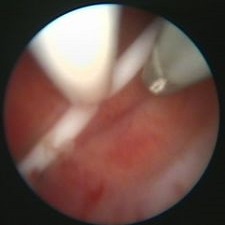

Nejčastější hysteroskopické nálezy

Rozrušení srůstů v dutině děložníRozrušení